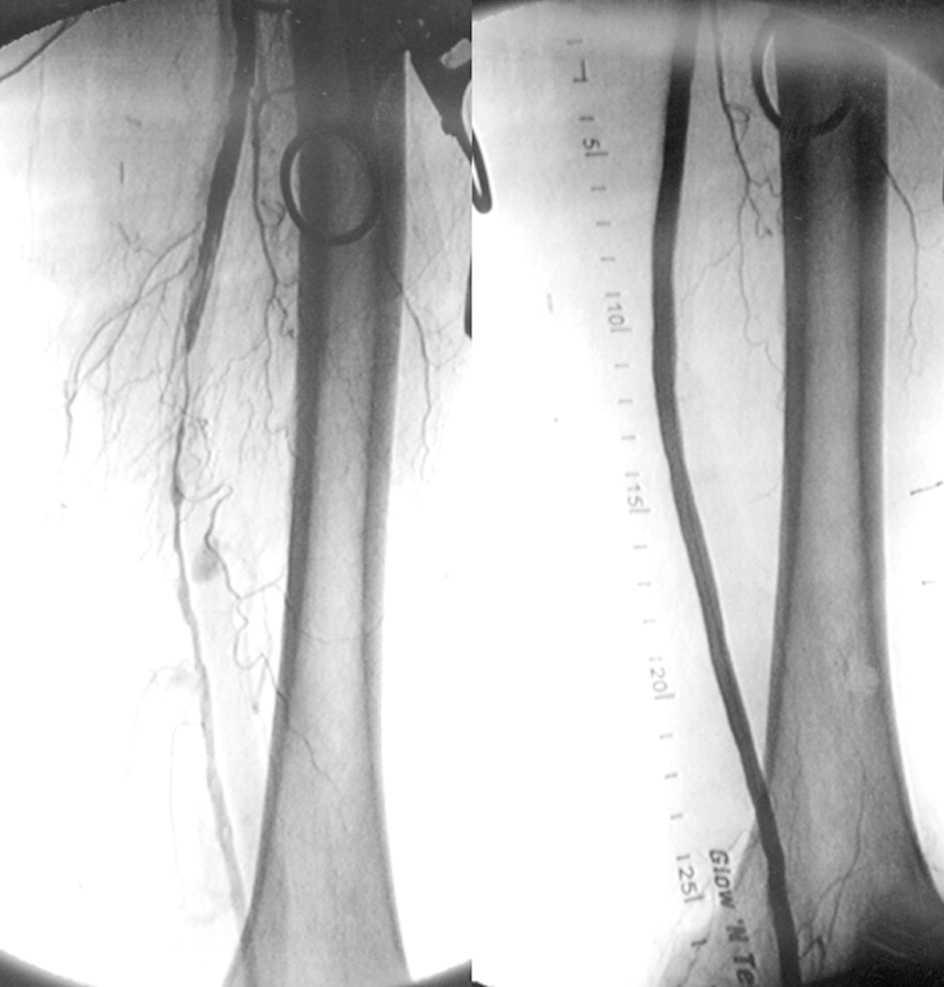

En pacientes con isquemia crónica y severa que tenían una vena safena adecuada para la revascularización quirúrgica, los resultados fueron significativamente mejores en el grupo quirúrgico que en el grupo de tratamiento endovascular. Para aquellos pacientes que carecían de una vena safena adecuada para la cirugía, los resultados en los dos grupos fueron similares. New England Journal of Medicine, 7 de noviembre de 2022.